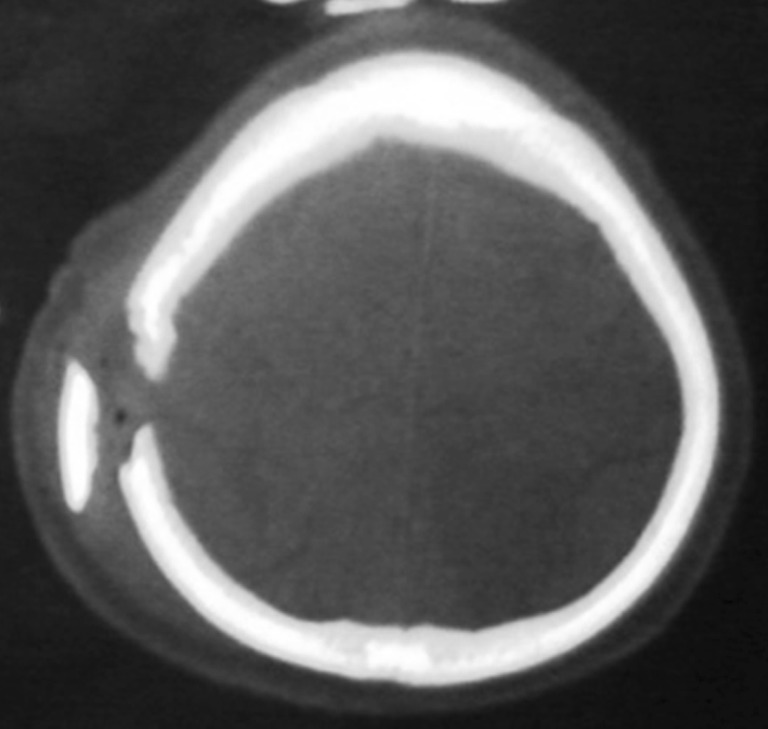

NCCT head is the investigation of choice as in other emergent head injuries (Figs. 2 and 3). It demonstrates the elevation of fractured segment as well as associated underlying intracranial injury and hematomas, all of which are associated with worse prognosis [5–10].

Fig. 2.

NCCT brain showing right parietal elevated skull fracture